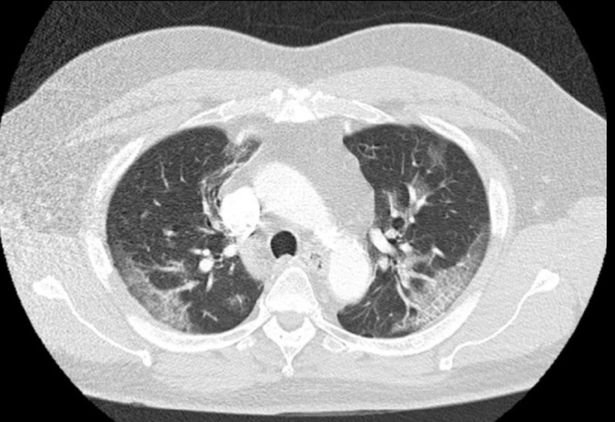

26 Ağustos 2020 Çarşamba 16:58The American Journal of Emergency Medicine'da yayımlanan bir makalede dört gün boyunca hıçkırık tutan bir adamda korona virüsü tespit edildiği belirtildi. Uzmanlar bunun "korona virüsünün yeni belirtisi" olabileceğini duyurdu. Makalede, 62 yaşındaki Chicagolu bir adamın dört gün boyunca hıçkırdığı ve bunun aralıksız devam ettiği kaydedilirken, "Hiç semptom göstermiyordu ve ateşi ölçüldüğünde de 37.3 derece ateşi vardı. Fakat hastaneye kaldırılıp testler derinleşince durum ortaya çıktı. Corona virüsü testi pozitif çıktı ve ciğerlerinin kapasitesinin de düştüğü görüldü.